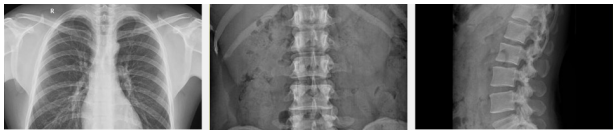

新东方1000MC型数字平板成像系统(DR),高科技优质产品,采用大尺寸移动 平板和政绩一体化设计,彻底解决了盲区成像,实现了全能临床应用,智能化设计,实现了自动跟随功能,采用一体化融合使系统更加稳定,多通道频域滤波技术,针对数字领域的图像分别进行专门的调整,保障所有影像细节达到最优化。